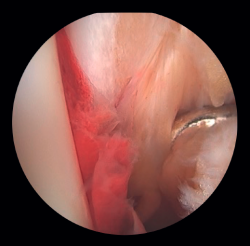

Si la lesión del deltoideo compromete solo a la parte anterior, podremos realizar la reinserción de forma artroscópica mediante implantes reabsorbibles. Si la desinserción del deltoideo es completa, preferimos realizar la reinserción de forma abierta por la dificultad que entraña colocar los implantes en la zona posterior del maléolo y el riesgo de lesión neurovascular (Figura 5).